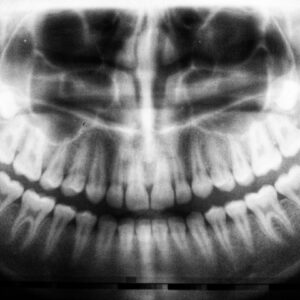

Can You Have Cavities In Your Dental Roots

When you think about your teeth, the first things that often come to mind are their visible surfaces—the enamel that gleams when you smile or the intricate patterns of your…